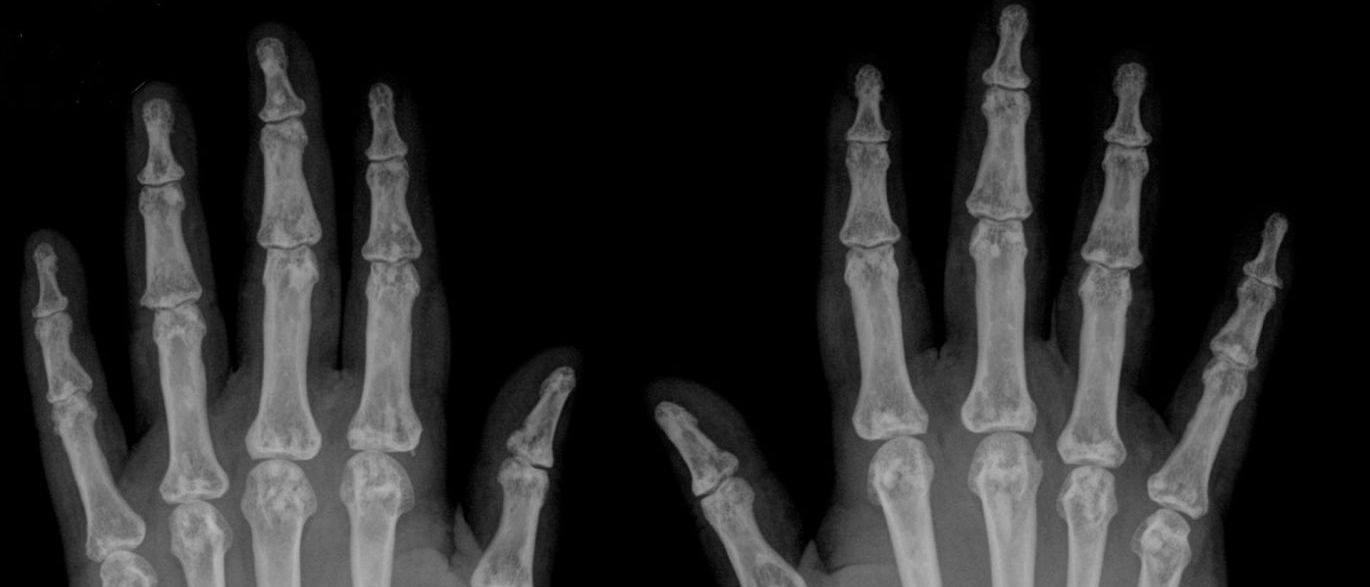

Cientistas da UC Davis Medical Center, Estados Unidos, descobriram que quando estalamos os dedos, o espaço existente entre os ossos se expande e o líquido articular, que também é uma das fontes de nutrição para a cartilagem, se torna insuficiente para preencher a lacuna

Além disso, o som dos estalos é causado pela liberação rápida desses gases. Isso é o que faz com que as juntas aumentem entre 15% a 20% seu volume. Esses gases contém aproximadamente 80% de dióxido de carbono. E você só conseguirá estalar novamente quando esses gases voltarem para seu devido lugar.

Segundo especialistas que analisaram dedos de pessoas que possuem esse hábito, o movimento articular aumenta sua amplitude logo depois do estalo, isso significa uma espécie de “aquecimento” das articulações, o que torna essa prática uma boa tática preventiva de doenças articulares.

A pesquisa também mostrou que as pessoas que tem esse hábito não possuem as juntas mais grossas, inchaços, nem sofrem de artrite. O que pode desmitificar a ideia de que quem estala os dedos fica com eles mais grossos.